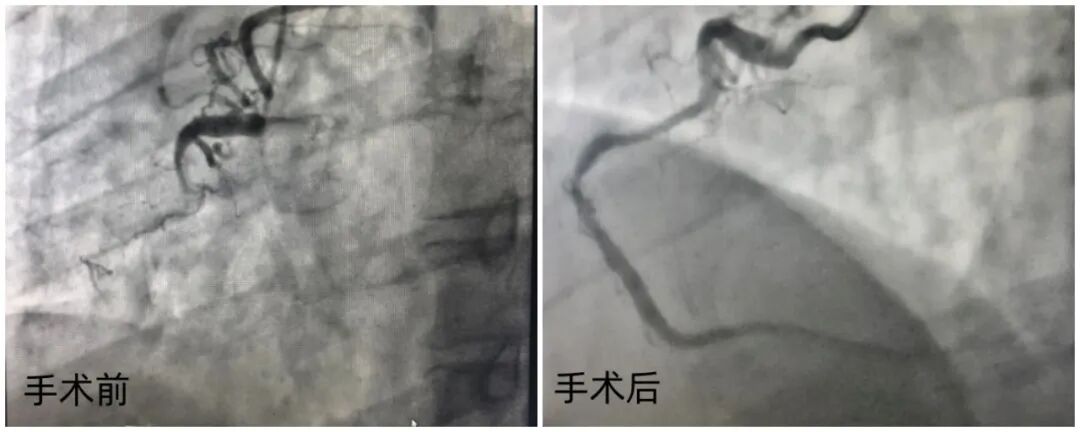

Clinical Challenge Fuwai Hospital recently managed a 43-year-old male with dual-segment Chronic Total Occlusions (CTO) in the Right Coronary Artery (RCA). Angiography revealed severe 3D tortuosity across both segments. This specific anatomy poses significant risks of vessel perforation and equipment delivery failure during recanalization.

Patient Benefit The 180-minute procedure achieved full RCA recanalization with TIMI 3 flow. The vessel's natural morphology was perfectly preserved. By achieving a "scaffold-free" reconstruction, the patient’s long-term risk of Major Adverse Cardiovascular Events (MACE) is significantly minimized.